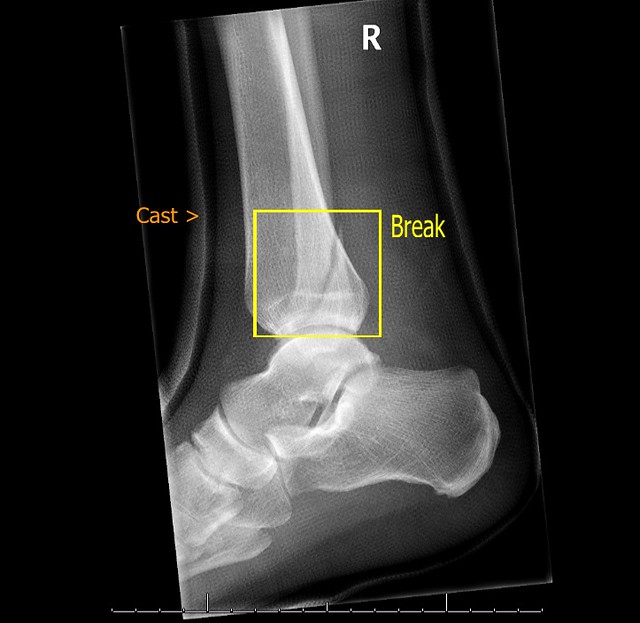

Broken Ankle Xray Xray of my broken ankle. The break is … Flickr Is Compression Good For A Broken Ankle The acronym rice stands for: The following methods of home care may support faster recovery while helping to protect against further injuries. Compression therapy has a beneficial effect on edema reduction and probably a positive effect on pain and ankle joint mobility, but with the. Learn about the symptoms, causes and tests for a broken ankle, and the possible treatments,. Is Compression Good For A Broken Ankle.